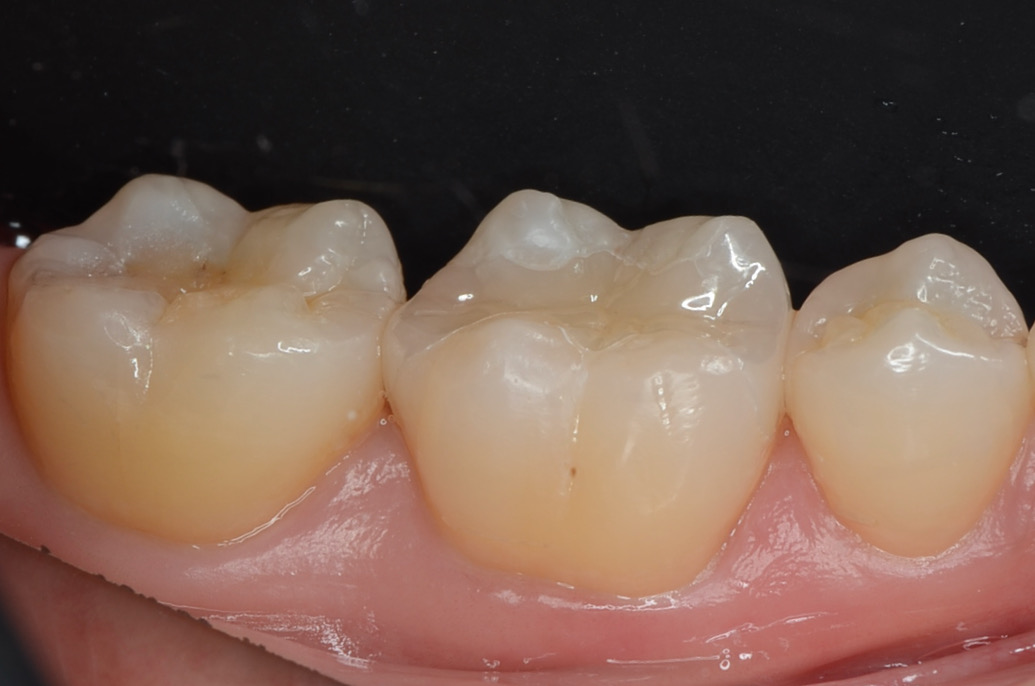

研磨終了

噛み合わせの調整をした後に、」段差の部分をしつこく研磨します。 -

-